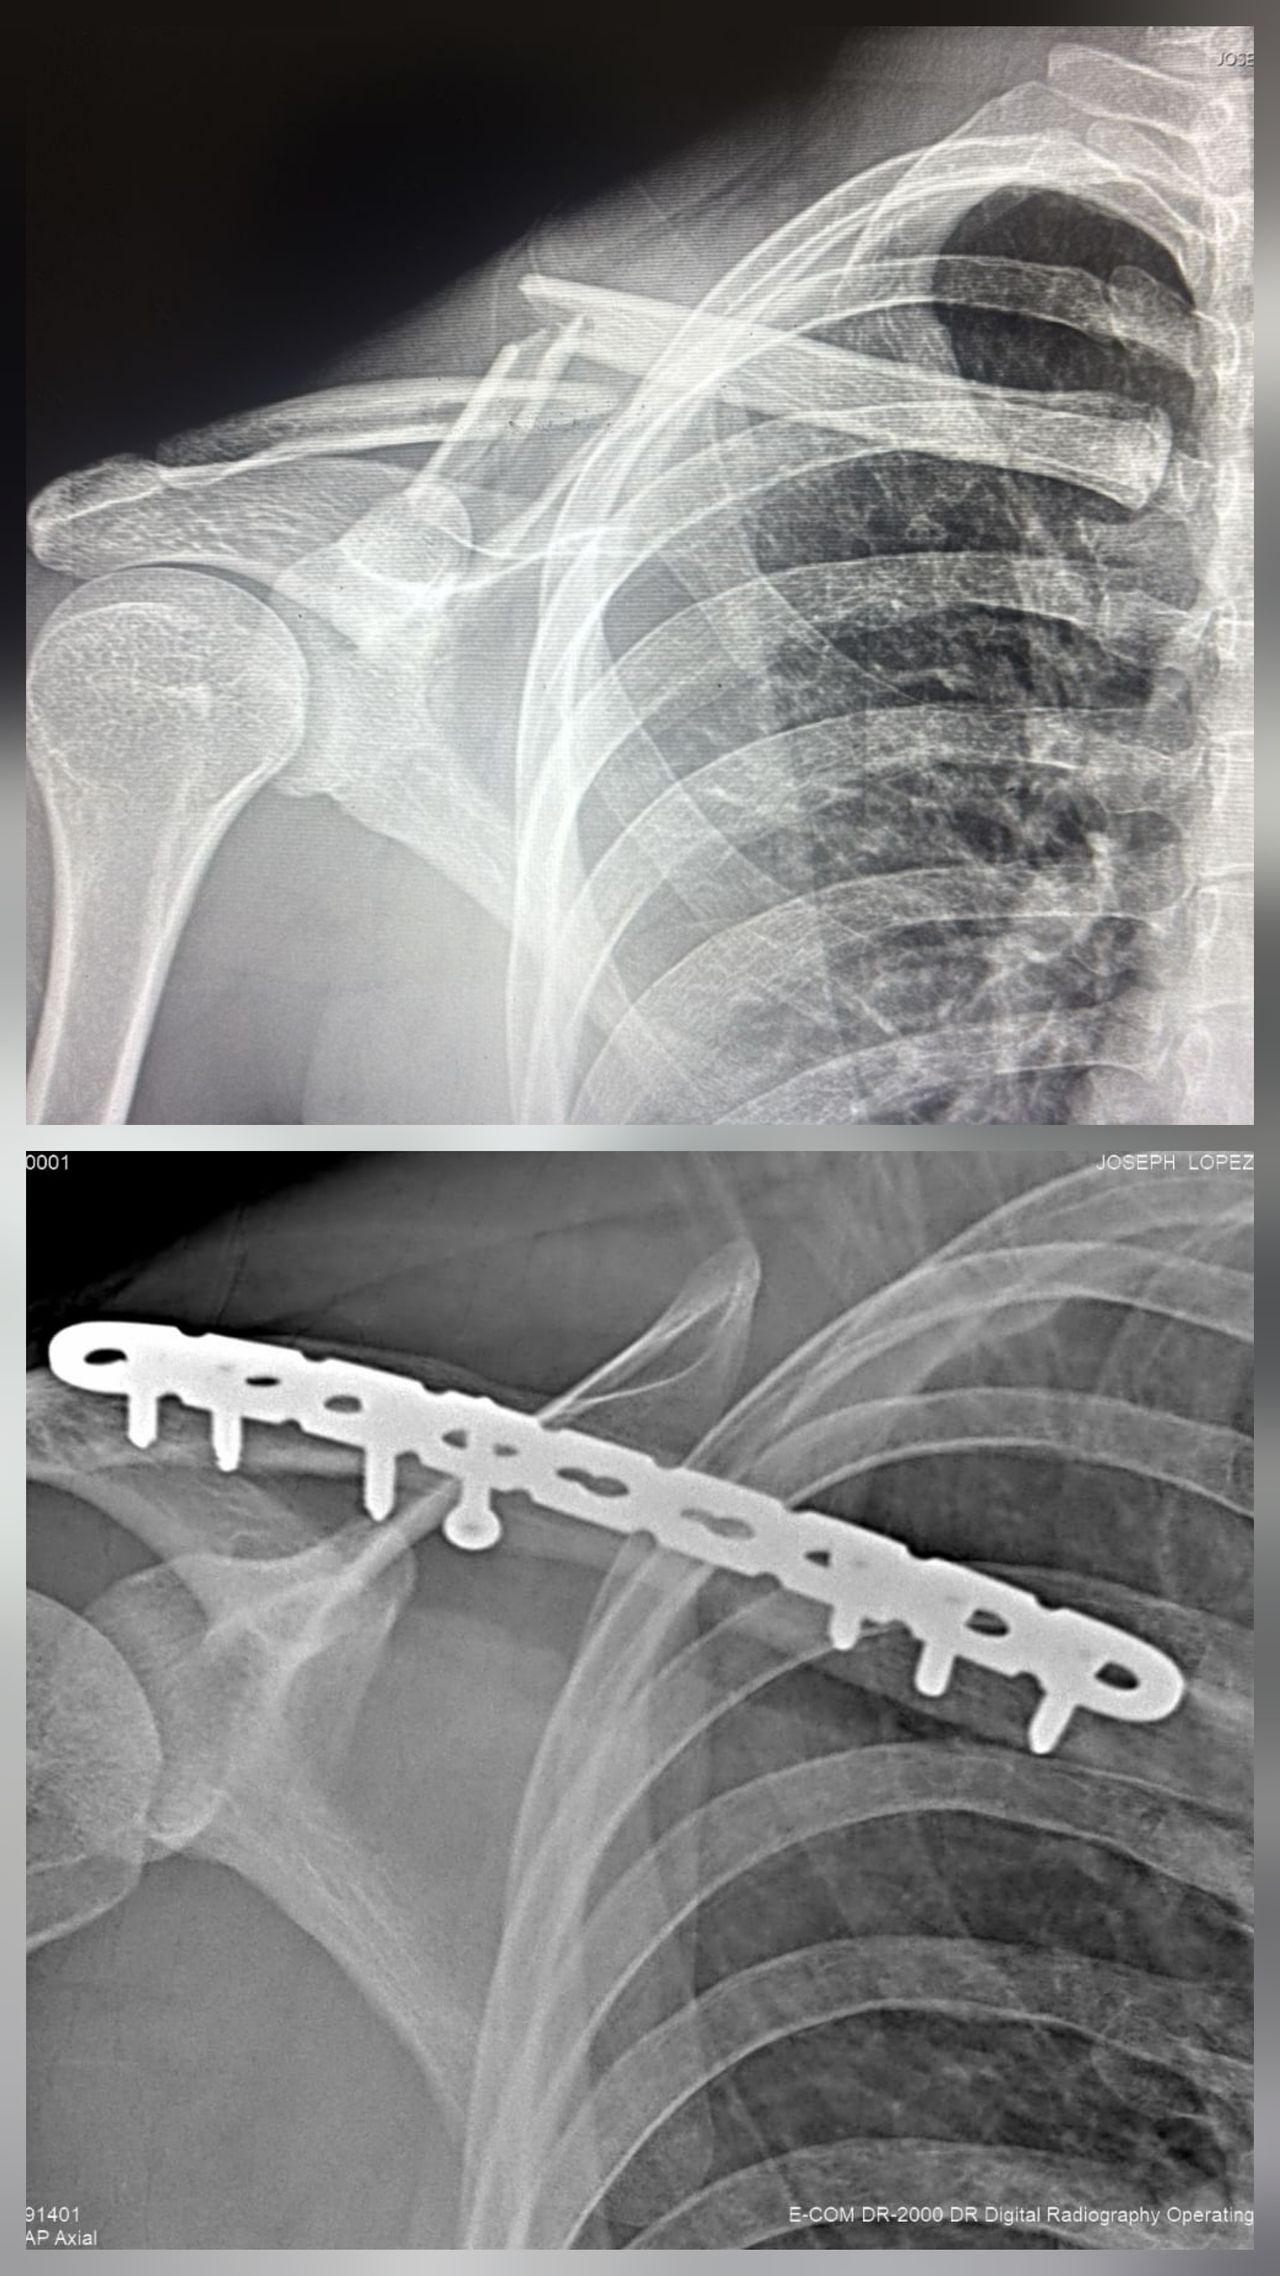

Mis habilidades más fuertes son el manejo de padecimientos de rodilla, cadera y hombro, así como procedimientos quirúrgicos asociadas a enfermedades degenerativas, fracturas y luxaciones.